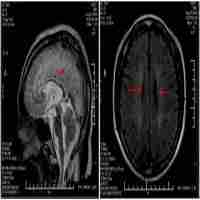

| Abstract | Hereditary spastic paraplegias (HSP) are a heterogeneous group of neurodegenerative disorders leading to progressive spasticity of the lower limbs. Here, we describe clinical and genetic features in an Italian family affected by autosomal recessive HSP (ARHSP) with mental impairment and thin corpus callosum (TCC). In both affected subjects, genetic analysis revealed the presence of a homozygous small deletion (733_734delAT) leading to a frameshift (M245VfsX) within the coding region of SPG11 gene, encoding spatacsin. This finding is the first independent confirmation that spatacsin loss of function mutations cause ARHPS-TCC. |